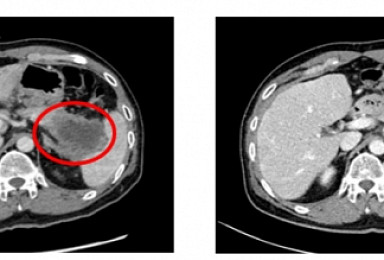

젬백스 리아백스주, 말기췌장암 환자서 '종양감소 효과' 확인